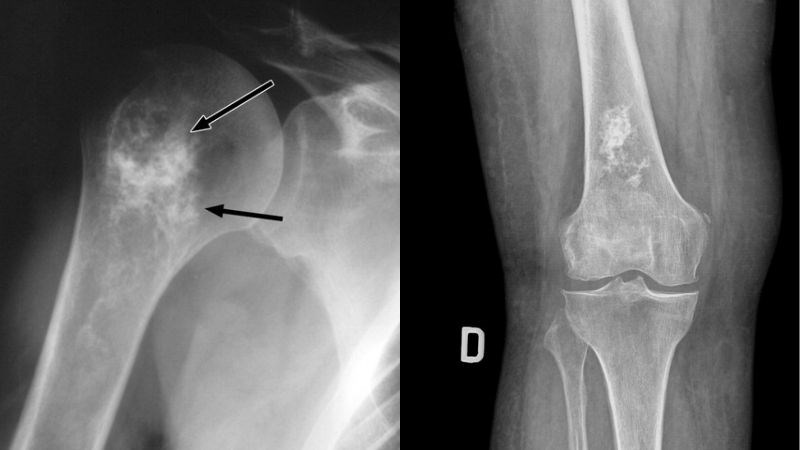

Sau khi được kiểm tra, bạn có thể được đề nghị chụp X-quang vùng bị ảnh hưởng để tìm kiếm bất kỳ vấn đề nào trong xương.

Nếu X-quang cho thấy những vùng bất thường, bạn sẽ được giới thiệu đến bác sĩ phẫu thuật chỉnh hình (chuyên gia về xương) hoặc chuyên gia ung thư xương để đánh giá thêm.

Chụp X-quang nhằm chẩn đoán ung thư xương